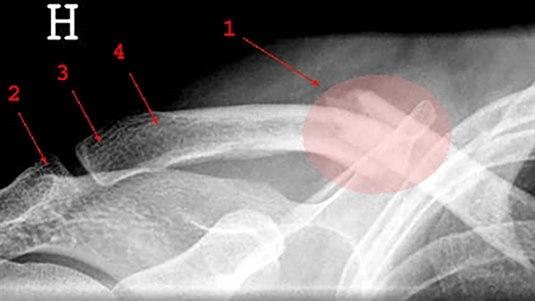

Kragebeinsbrudd forekommer hyppig, spesielt hos barn og unge. Over halvparten av bruddene skjer hos barn under 12 år. 80 prosent av bruddene sitter i midtre tredjedel, 15 prosent i ytre (distale) tredjedel og 5 prosent i indre (mediale) tredjedel. Kragebeinsbrudd kan oppstå som følge av direkte slag mot kragebeinet, støt mot skulderen fra siden, fallskader. Hos voksne kreves en større kraft for å brekke kragebeinet. Tilheling skjer langsommere hos voksne enn hos barn, og risikoen for komplikasjoner er større.

Kragebeinsbrudd behandles vanligvis uten operasjon med armen i fatle en kort periode (konservativ behandling). Indikasjon for operasjon er vanlig dersom beinet er blitt forkortet med mer enn 15 mm, eller at det er mer enn 15 mm avstand mellom bruddendene, eller at det foreligger et brudd med mer enn tre bruddstykker.

Feil sammenvoksning (malunion) av bruddendene - av ulike grader - kan oppstå hos opptil 2/3 av pasientene etter konservativ behandling, vanligvis er forkortning problemet. Manglende sammenvoksning (nonunion) eller dannelse av et falskt ledd (pseudartrose) kan også oppstå hos cirka 5 prosent av pasientene, enten de blir operert eller ikke. Operativ behandling gir eller bør gi korrekt stilling av bruddet etter inngrepet hos cirka 95 prosent.